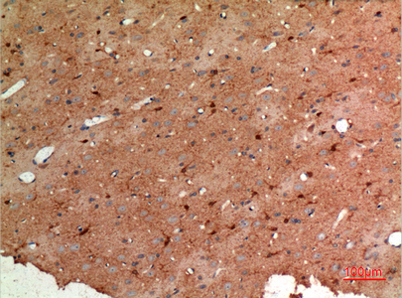

| Dilutions: | Western Blot: 1/500 - 1/2000. IHC-p: 1:100-300 ELISA: 1/20000. Not yet tested in other applications. |

| Background: | This gene encodes a member of the class I fructose-biphosphate aldolase gene family. Expressed specifically in the hippocampus and Purkinje cells of the brain, the encoded protein is a glycolytic enzyme that catalyzes the reversible aldol cleavage of fructose-1,6-biphosphate and fructose 1-phosphate to dihydroxyacetone phosphate and either glyceraldehyde-3-phosphate or glyceraldehyde, respectively. [provided by RefSeq, Jul 2008], |